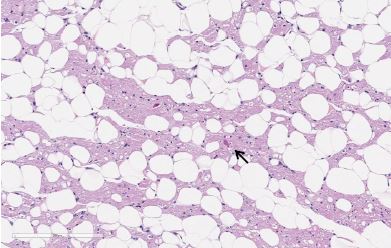

病理検査

通常の病理検査に加え、重要な所見の場合は、電子顕微鏡での検査も実施しています。